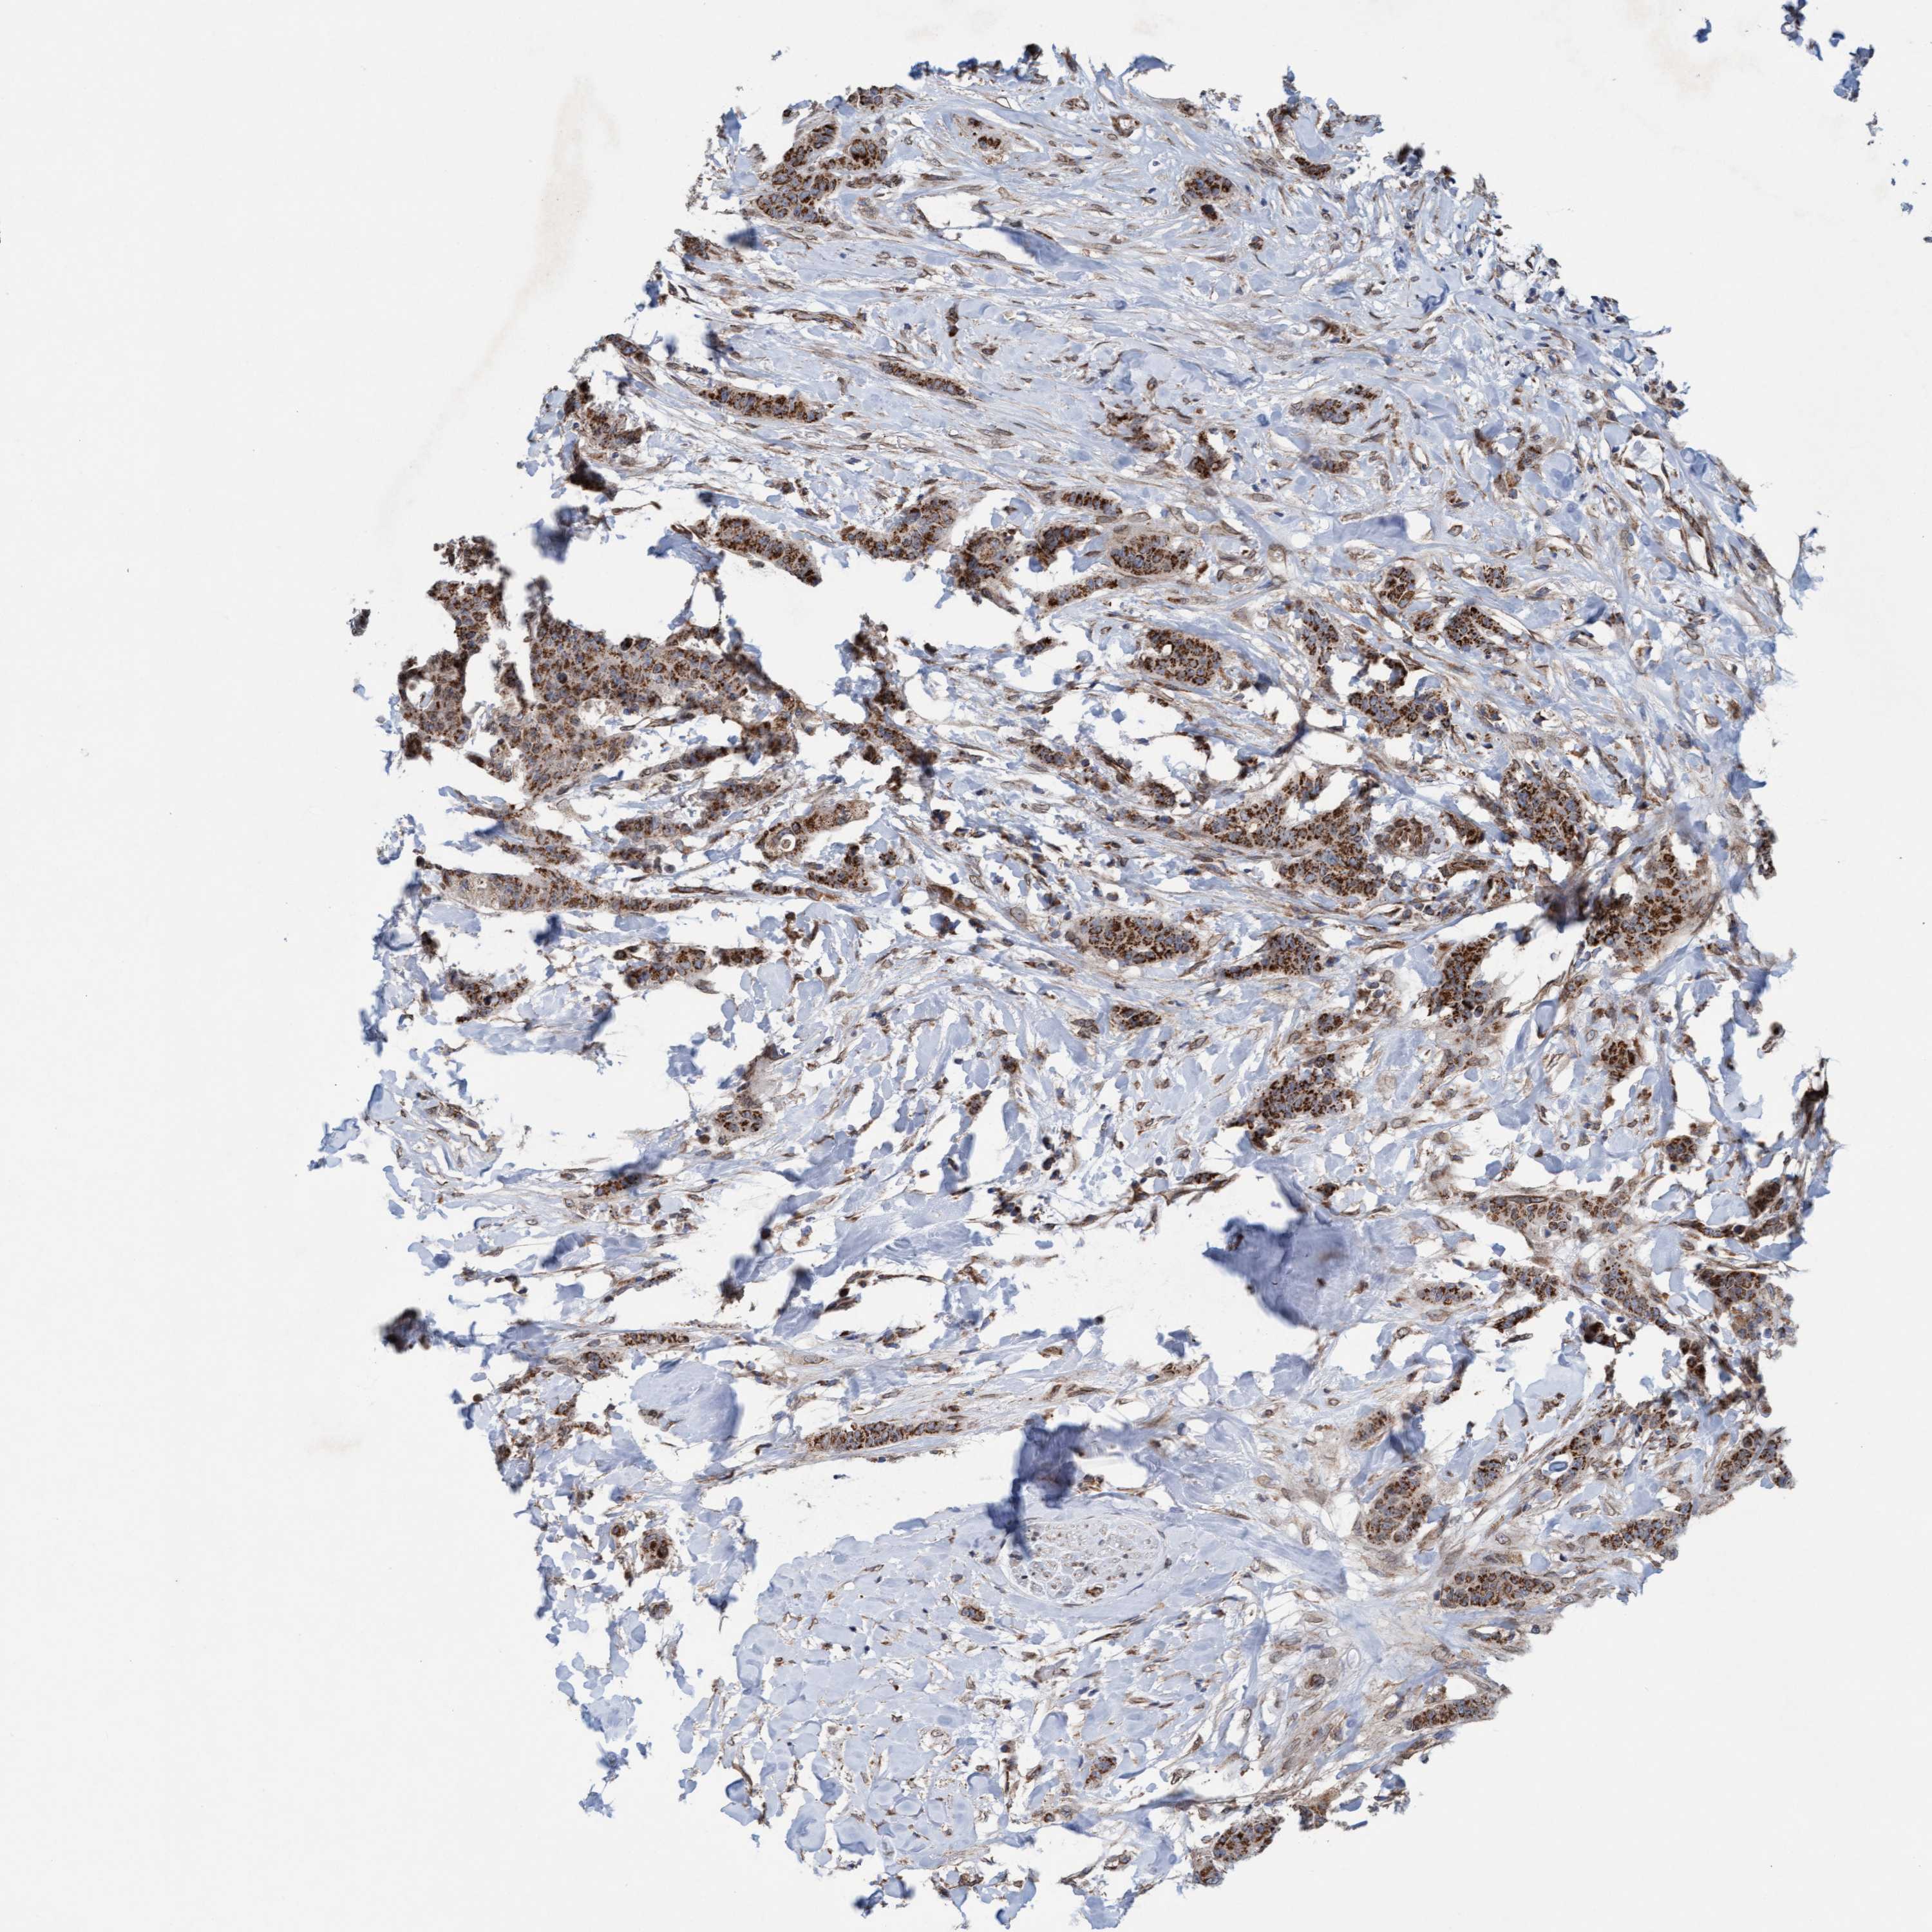

CANCER BREAST CANCER Show tissue menu

BRCA TCGA BRCA VALIDATION PROTEIN EXPRESSION